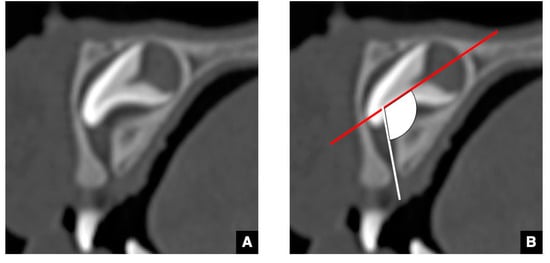

2.1. CT Images of the GT in the Successional Tooth